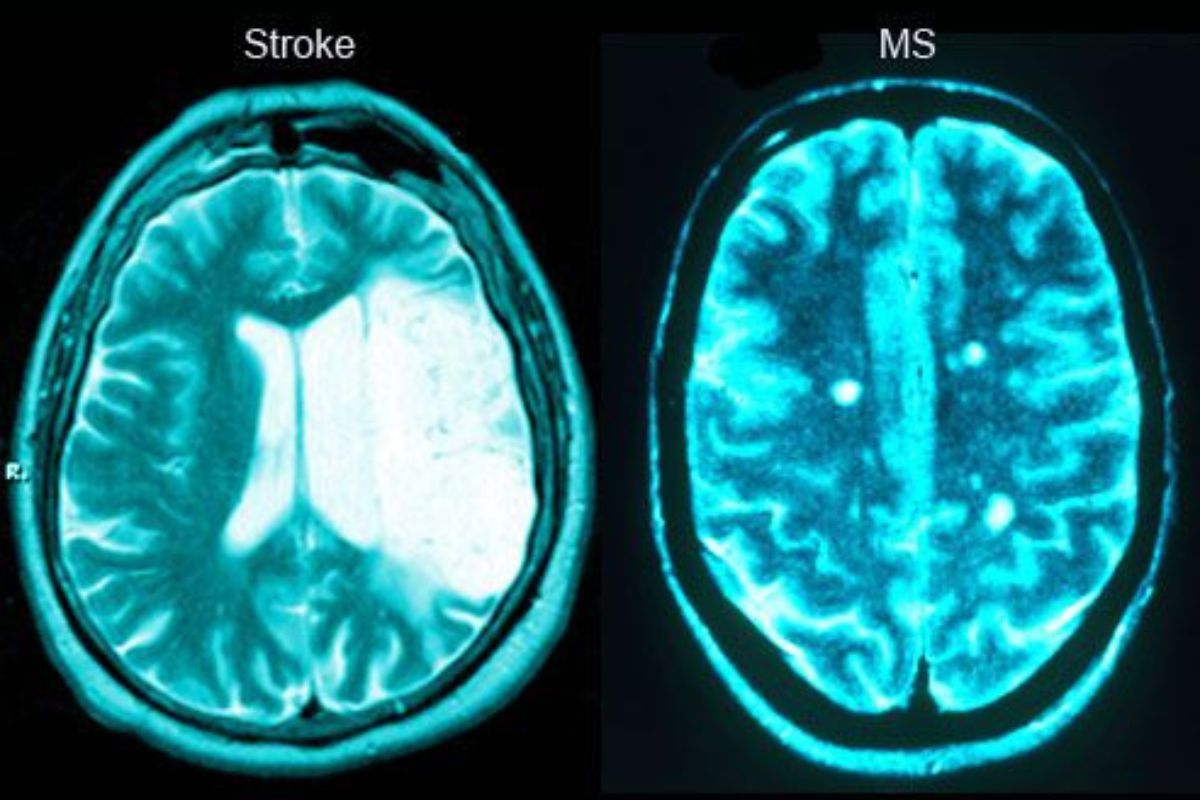

Salah satu kekhawatiran terbesar saat mengalami kelumpuhan wajah adalah kemungkinan stroke. Namun, penting untuk memahami bahwa Bell’s Palsy berbeda dengan stroke, meskipun memiliki gejala yang sekilas mirip.

Pada Bell’s Palsy, kelumpuhan biasanya hanya terjadi pada satu sisi wajah tanpa disertai kelemahan pada anggota tubuh lainnya. Sementara itu, stroke sering disertai gejala tambahan seperti kelemahan pada tangan atau kaki, gangguan bicara, hingga penurunan kesadaran.

Perbedaan ini sangat penting karena penanganan stroke memerlukan tindakan medis darurat, sedangkan Bell’s Palsy umumnya dapat pulih dengan pengobatan yang tepat. Oleh karena itu, pemeriksaan oleh dokter saraf sangat diperlukan untuk memastikan diagnosis yang akurat.

Selain itu, dokter saraf mungkin akan melakukan pemeriksaan tambahan untuk memastikan bahwa kondisi tersebut bukan disebabkan oleh penyakit lain, seperti stroke atau tumor. Pemeriksaan ini bisa meliputi MRI, CT scan, atau tes saraf tertentu.